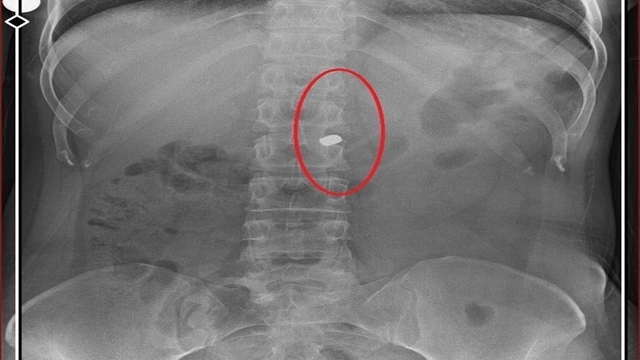

İlyas Sarıkaya, sevgilisi Fatma O.'yu da 8 kurşunla vurup, yaraladı. Arkadaşı Özaslan'ın cesedini önce çarşafa sonra da streç filme sarıp bantlayan Sarıkaya, eczaneden aldığı sargı bezi ve ilaçlarla pansumanını yaptığı sevgilisine yaralı haldeyken 21 gün boyunca cinsel saldırıda bulundu.